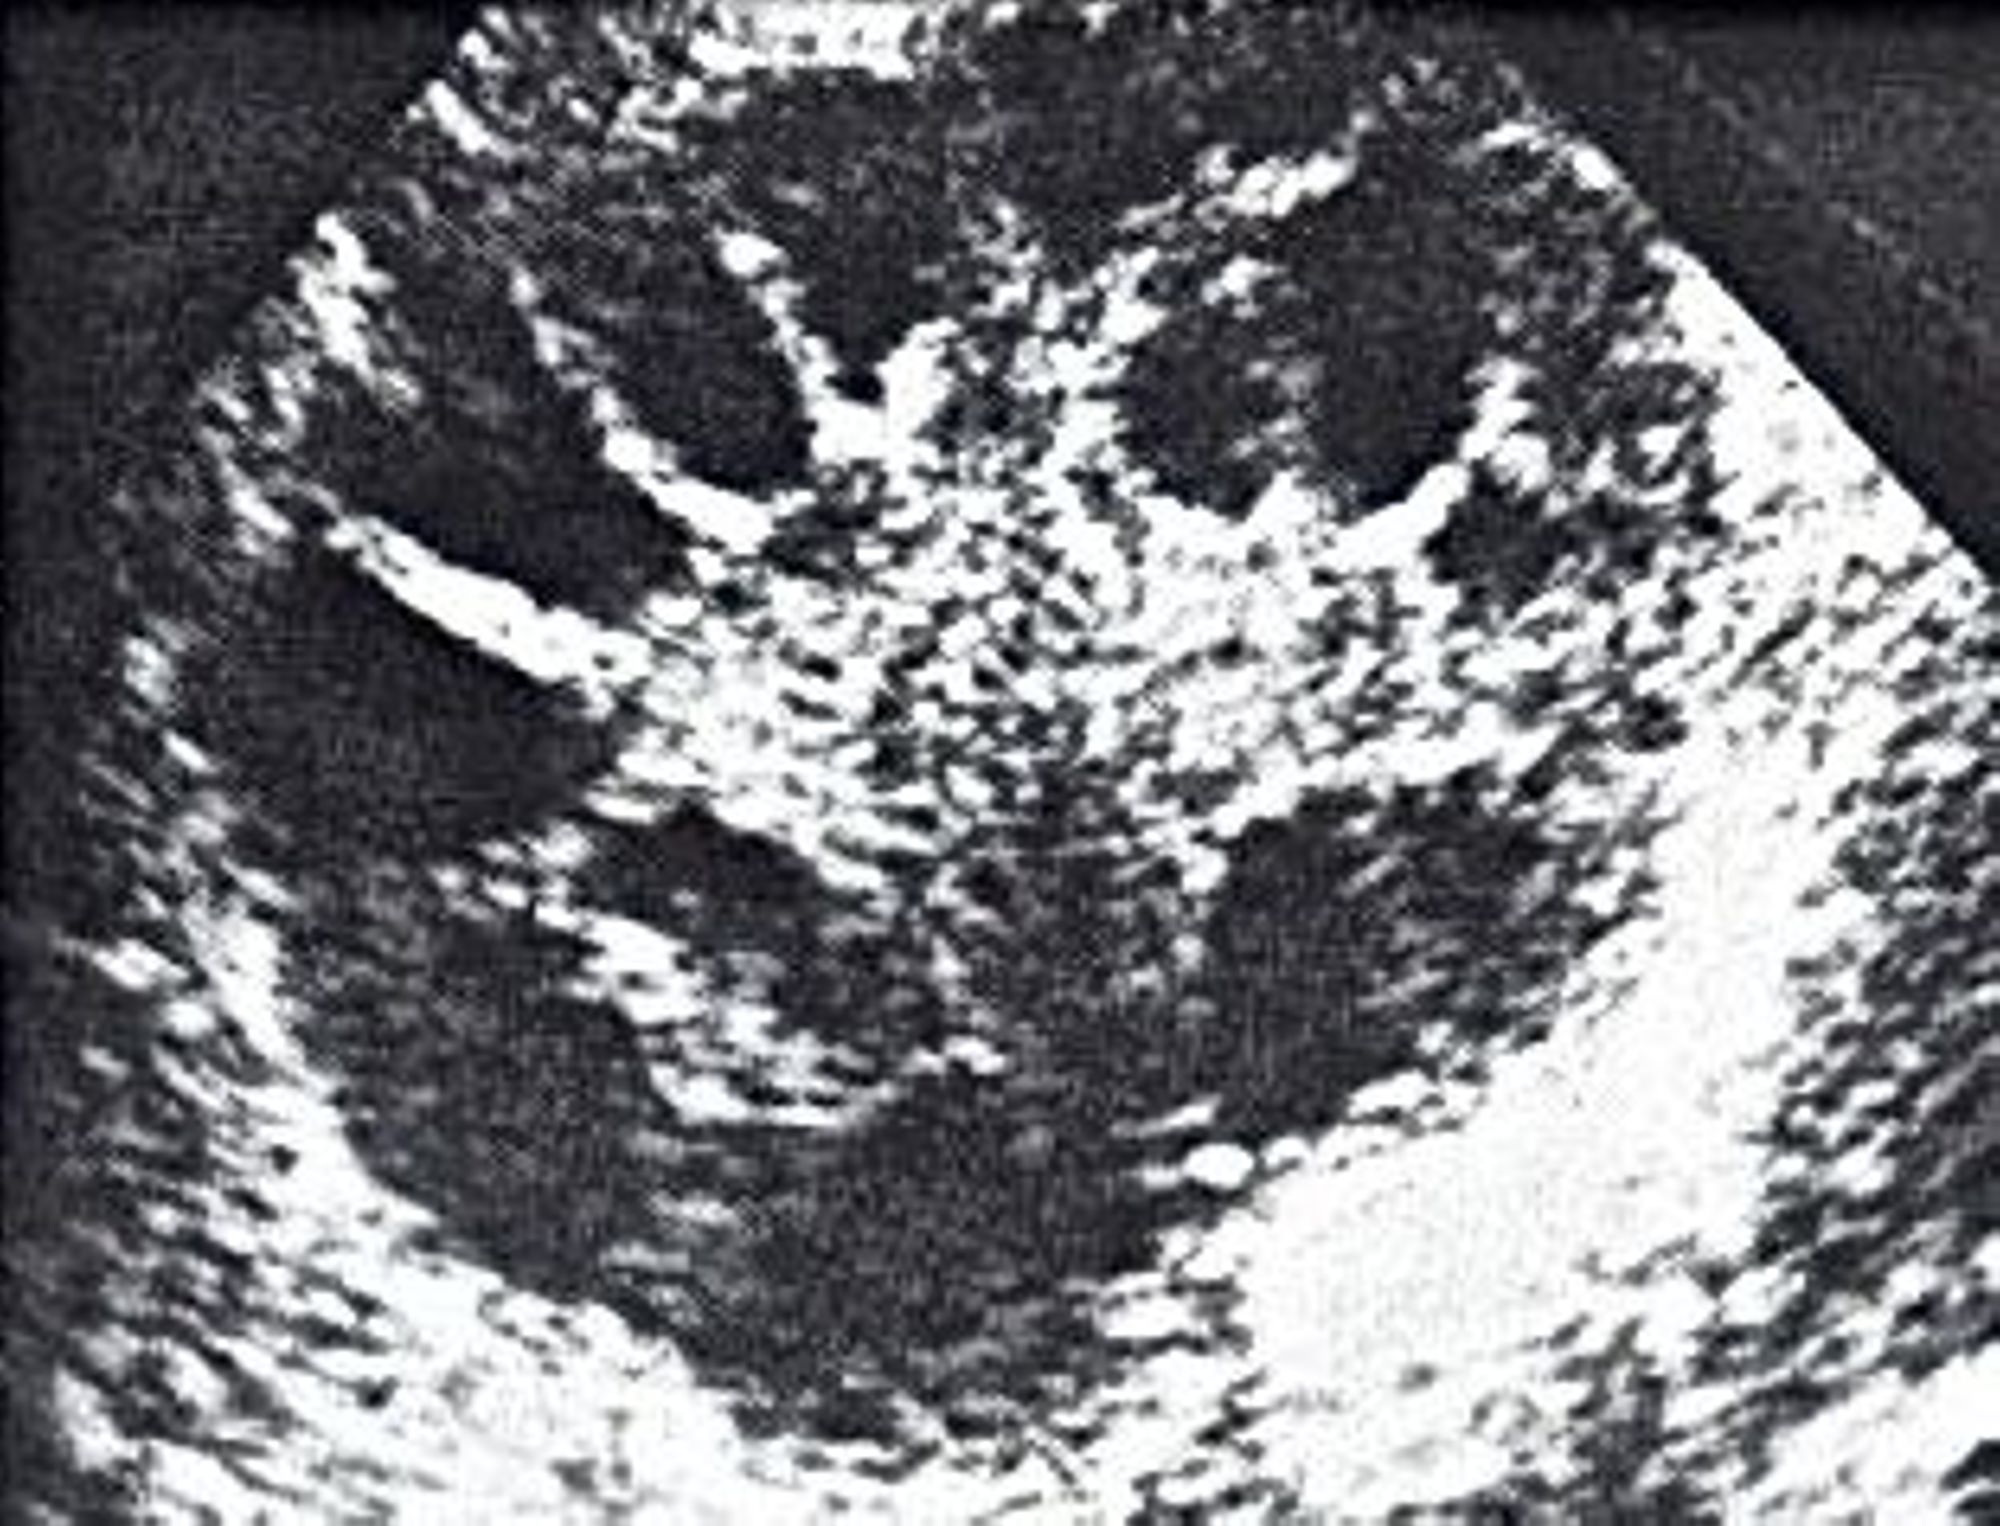

Les signes cliniques sont ; des règles espacées voire absentes, de l’acné, une pilosité excessive, une chute des cheveux, un surpoids. Si vous présentez ces symptômes, le médecin vous prescrira une analyse de sang et une échographie pelvienne qui permettra de compter vos ovocytes et ainsi de confirmer, ou non, leur nombre trop important.